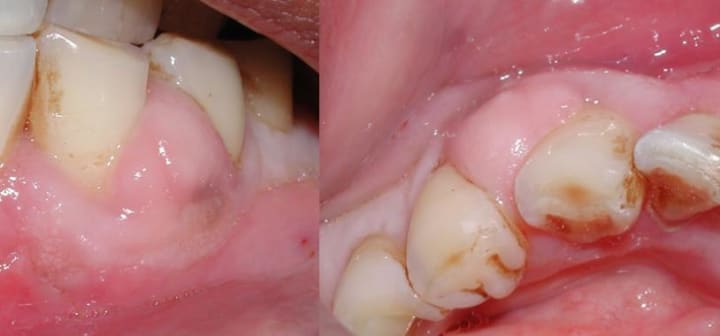

Teeth with Abscesses

An abscess in the tooth is an infection produced by a pocket of pus in the tissue around the tooth. Abscesses are highly dangerous conditions that can lead to major complications if not addressed quickly. When a tooth's pulp dies due to injury or decay, germs begin to proliferate from the dead tissue that is left behind. This bacteria will ultimately move from the decaying tooth's root into the tissue below, forming a pocket of pus - the abscess.

Gum disease can potentially cause an abscessed tooth.. Gum disorders cause the gums to move back and away from the teeth, resulting in pockets. When one of the compartments becomes blocked, germs can develop and spread or become clogged. When this happens, an abscess will form beneath the surface of the gums and will cause swelling as it grows and spreads.

Severe pain in the afflicted area, red or swollen gums, a terrible taste in your mouth, swelling surrounding the area or the jaw, and potentially a high temperature are all indicators of an abscessed tooth. An abscess causes terrible pain and usually has a negative impact on the region. Whatever you do, the agony appears to become worse.